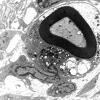

PERIPHERAL NEUROPATHY

7B CIDP (2)